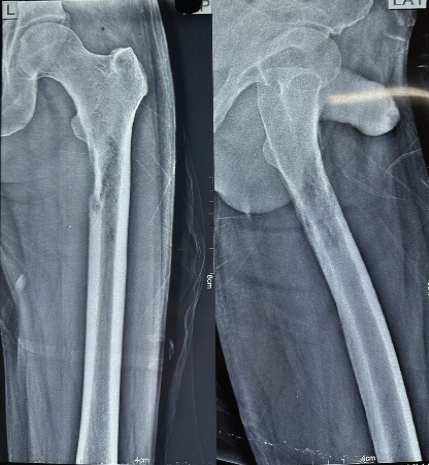

Plain radiographs of the left hip with femur anteroposterior and lateral views revealed a left subtrochanteric lytic lesion confined within the cortex (Fig. 4).

Figure 4 : Postoperative anteroposterior (AP) and lateral radiographs of the left femur following intramedullary fixation with PFNA2 (Proximal Femoral Nail Antirotation 2). The radiographs show acceptable fracture reduction with proper implant positioning and interlocking. The PFNA2 provides biomechanical stability across the pathological lesion site.

Intervention

We planned surgical management with Proximal Femoral Nail Antirotation Asia II (PFNA2). The intraoperative sample was taken from the medullary cavity and was sent for histopathological examination. The post-operative X-ray (Fig. 2) showed acceptable fracture reduction, and the patient was mobilized off the bed from the 1st post-operative day with partial weight-bearing. Histopathological examination confirmed the diagnosis metastasis secondary to hepatocellular carcinoma. Patient was given 5 mg i/v zolendronic acid along with analgesics and antibiotics.